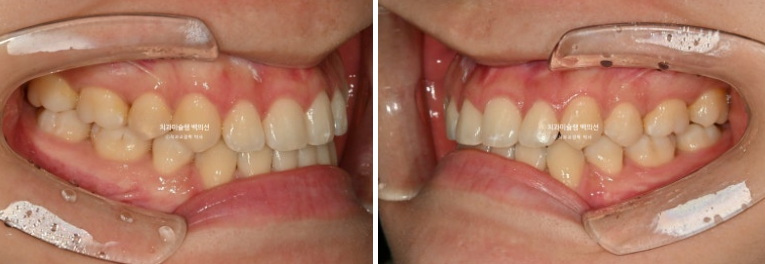

23.11~25.10

어긋나 있던 위아래 중심선이 일치되었습니다.

앞니가 거꾸로 물리는 반대교합이 해결되었습니다.